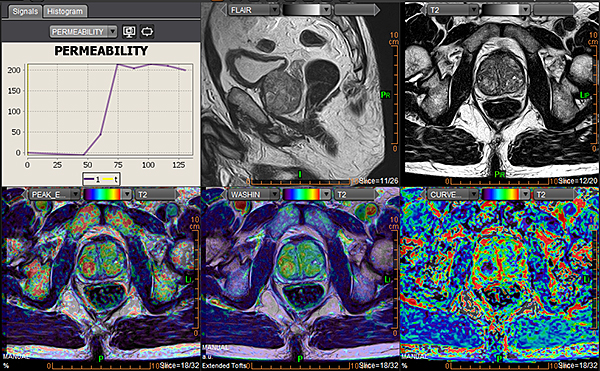

Magnētiskās rezonanses (MR) izmeklējums prostatai tiek veikts, lai detalizēti izvērtētu prostatas struktūru un patoloģiskas izmaiņas.

PI-RADS ir sistēma, ko radiologi izmanto, lai novērtētu prostatas MR attēlos redzamās izmaiņas un noteiktu, cik lielā mērā tās varētu būt saistītas ar prostatas vēzi.

PI-RADS vērtējums tiek izteikts ar ciparu no 1 līdz 5:

PI-RADS 1–2 nozīmē, ka ļaundabīga procesa iespējamība ir ļoti zema,

PI-RADS 3 – neskaidra atrade,

PI-RADS 4–5 – paaugstināta iespējamība, ka atradums varētu būt vēzis.

Svarīgi saprast, ka PI-RADS vērtējums pats par sevi nav diagnoze – tas tikai norāda, cik liels ir ļaundabīga procesa risks. Galīgo apstiprinājumu sniedz biopsija vai histoloģiska analīze.